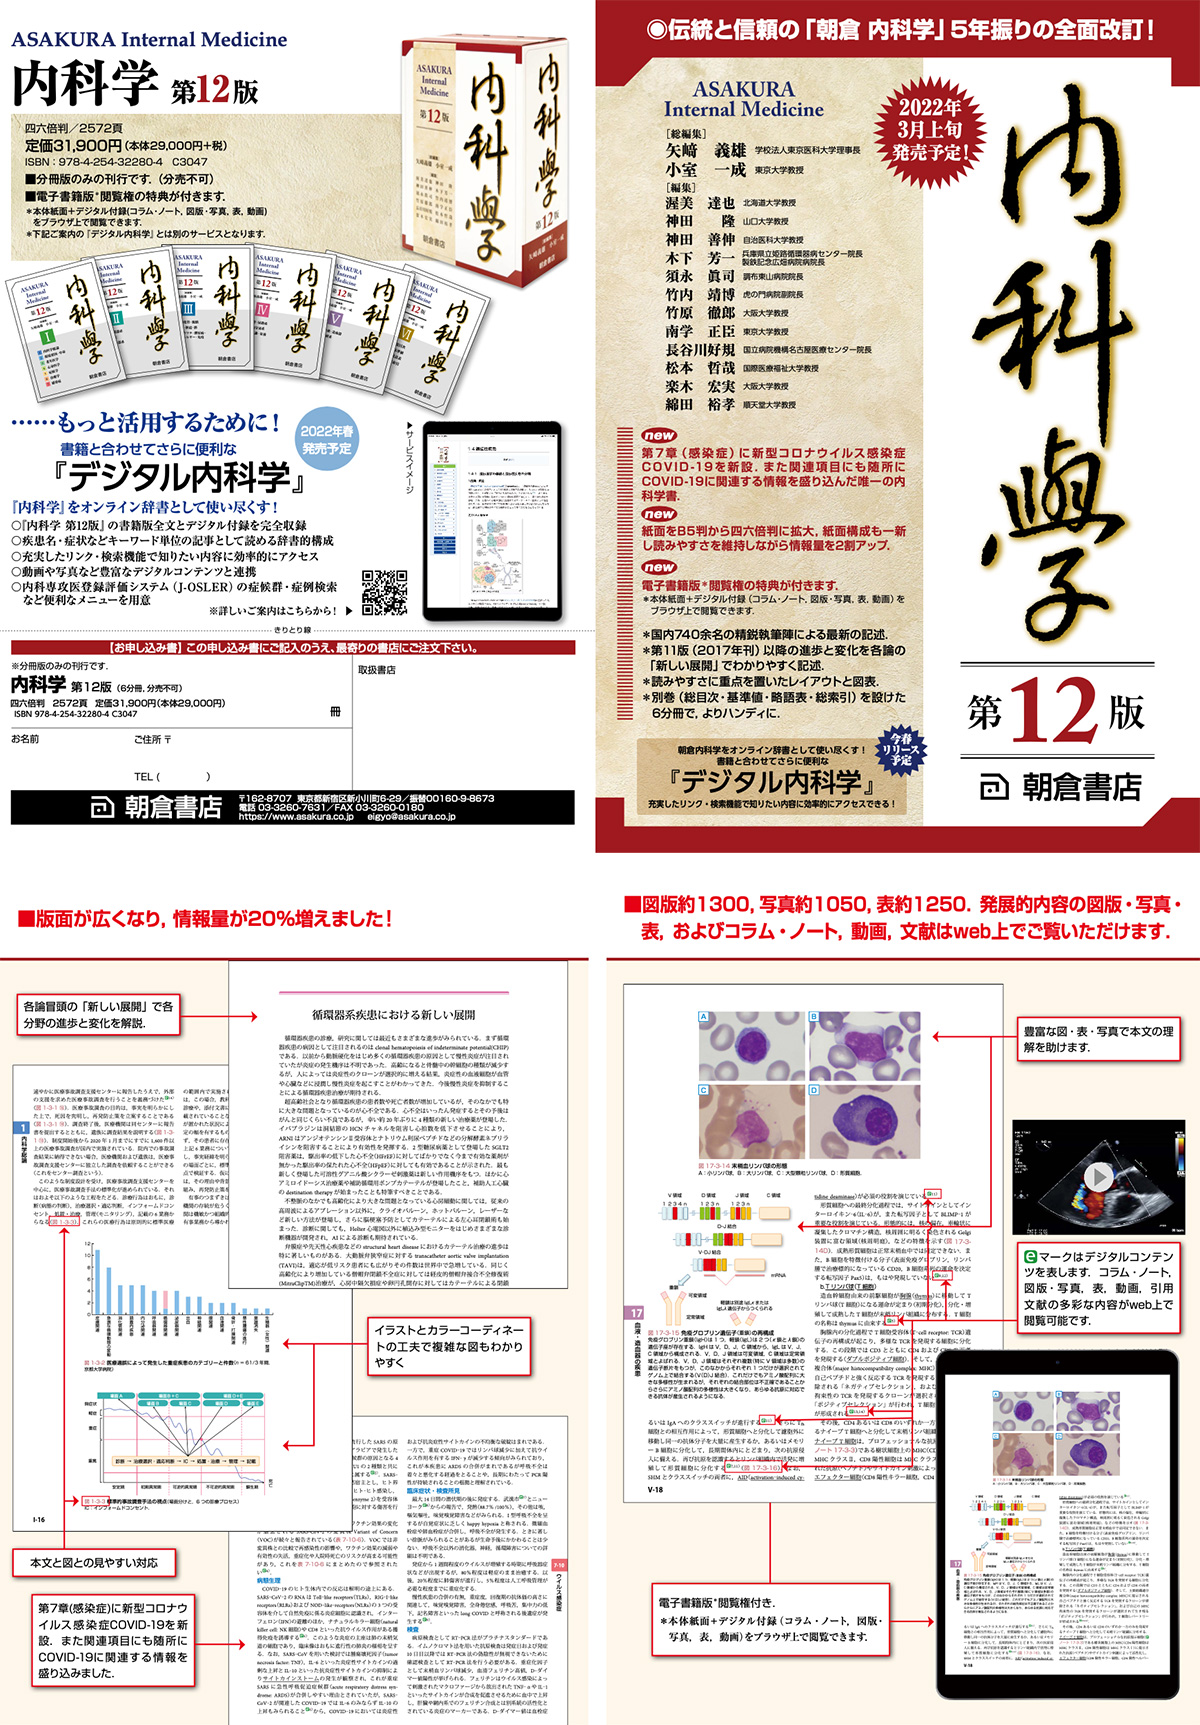

91RxeAK12UL.jpg, 朝倉内科学第12版』待望の全面改訂。鍼灸医学大辞典 デスク版/医歯薬出版/森和(大型本)。PC・タブレットでも閲覧可能!,

朝倉内科学第12版』待望の全面改訂。鍼灸医学大辞典 デスク版/医歯薬出版/森和(大型本)。PC・タブレットでも閲覧可能!, 朝倉内科学第12版』待望の全面改訂。歯科医療総研 院長先生のifをcanに 患者様・スタッフに求められ続ける医院づくり 状態良品 DVD4枚/CD1枚 ☆ 030s3D。PC・タブレットでも閲覧可能!,

朝倉内科学第12版』待望の全面改訂。歯科医療総研 院長先生のifをcanに 患者様・スタッフに求められ続ける医院づくり 状態良品 DVD4枚/CD1枚 ☆ 030s3D。PC・タブレットでも閲覧可能!, 朝倉内科学第12版』待望の全面改訂。購入者限定販売品!整体DVD【MB式整体 小顔調整術】松井真一郎 手技DVD。PC・タブレットでも閲覧可能!,

朝倉内科学第12版』待望の全面改訂。購入者限定販売品!整体DVD【MB式整体 小顔調整術】松井真一郎 手技DVD。PC・タブレットでも閲覧可能!, 朝倉書店『内科学』(第12版)デジタル付録

朝倉書店『内科学』(第12版)デジタル付録商品説明

出版社名:朝倉書店

発売日:1987年11月01日

ISBN:9784254321005

◆◆◆おおむね良好な状態です。医療情報研究所 歯周外科トレーニングコース 1〜3 状態良品 DVD3枚 ☆ 045s3D。中古商品のため使用感等ある場合がございますが、品質には十分注意して発送いたします。保存修復学総論 旧題 新編窩洞形成法 /永末書店/総山孝雄(単行本)。【毎日発送】

◆◆◆おおむね良好な状態です。医療情報研究所 歯周外科トレーニングコース 1〜3 状態良品 DVD3枚 ☆ 045s3D。中古商品のため使用感等ある場合がございますが、品質には十分注意して発送いたします。保存修復学総論 旧題 新編窩洞形成法 /永末書店/総山孝雄(単行本)。【毎日発送】